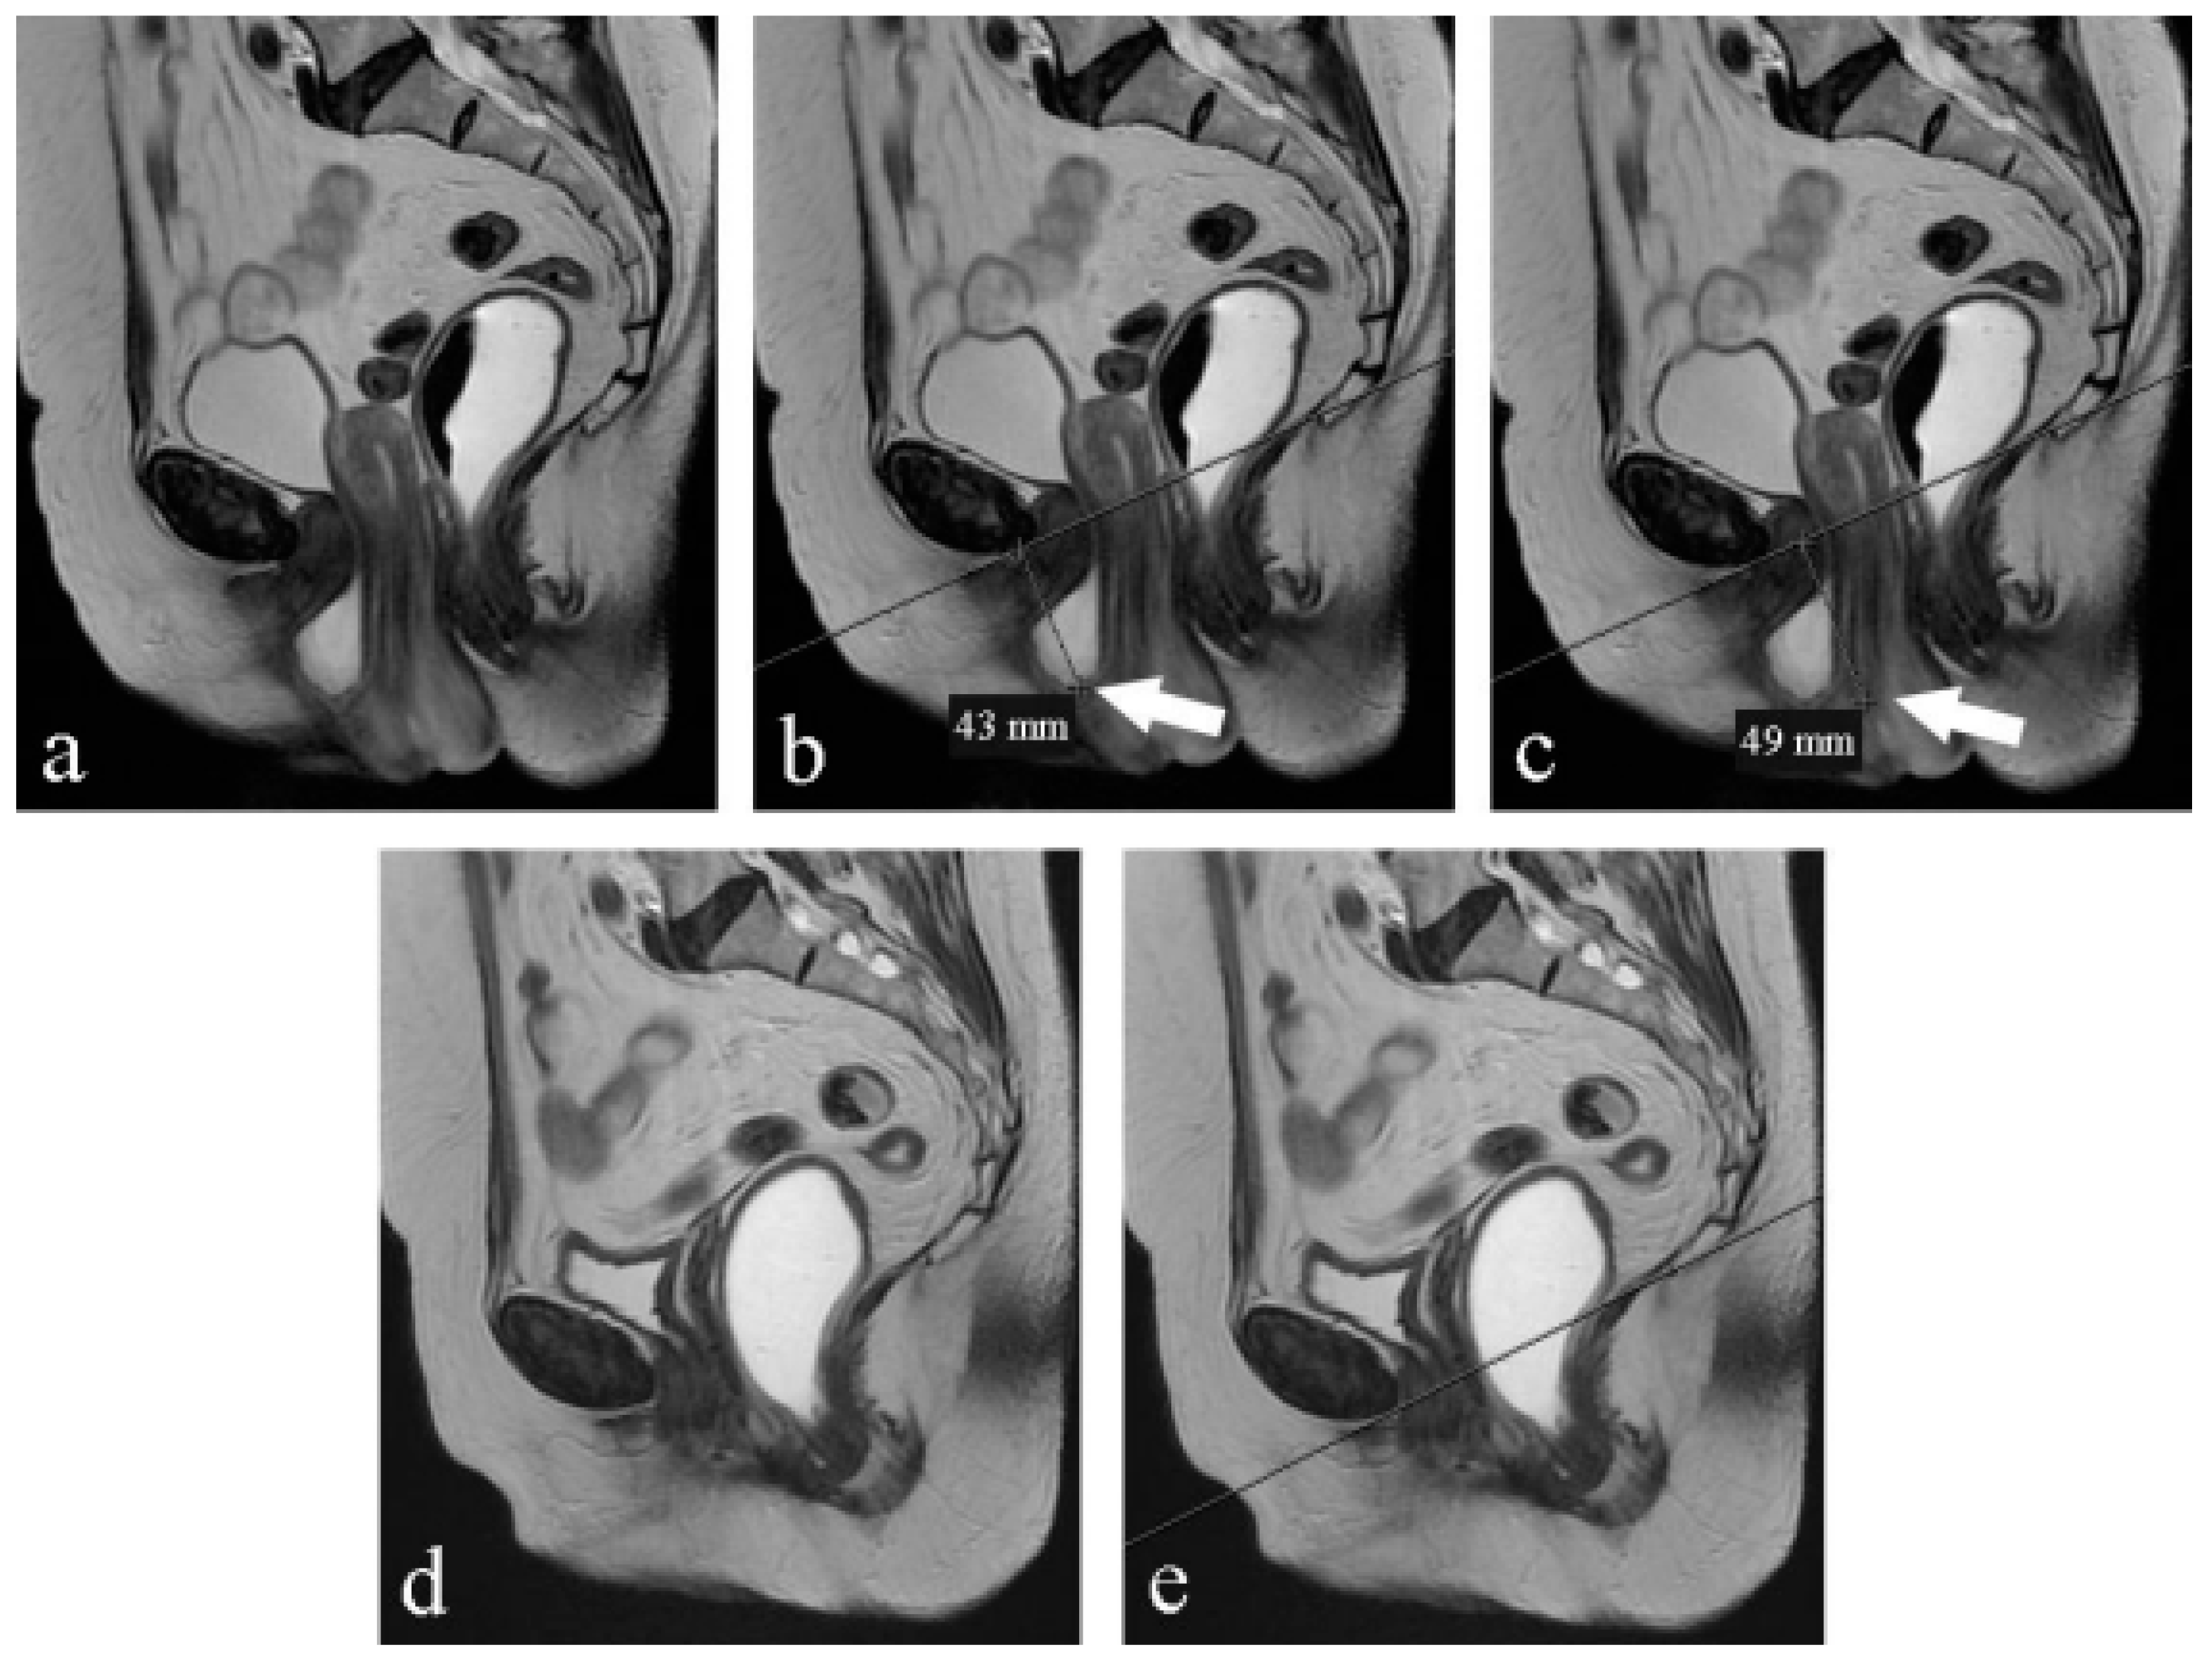

2.2. MRI Imaging Protocol

2.4. Sequences

- SSFSE (TR/TE, 708/90; flip angle, 90°; section thickness, 8 mm; bandwidth, 83.3 kHz; FOV, 34 cm; matrix, 384 × 224; several averages, 0.5; acquisition time for each image, 0.3 s) in the midsagittal plane, with sequential acquisition during contraction, rest, and straining;

- FIESTA (TR/TE, 3.3/1.4; flip angle, 45°; section thickness, 8 mm; bandwidth, 125 kHz; FOV, 35 cm; matrix, 224 × 224; a number of averages, 1; number of images, 20; acquisition time, 20 s) in the midsagittal plane, with continuous multiphase acquisition during contraction, rest, straining, and defecation.